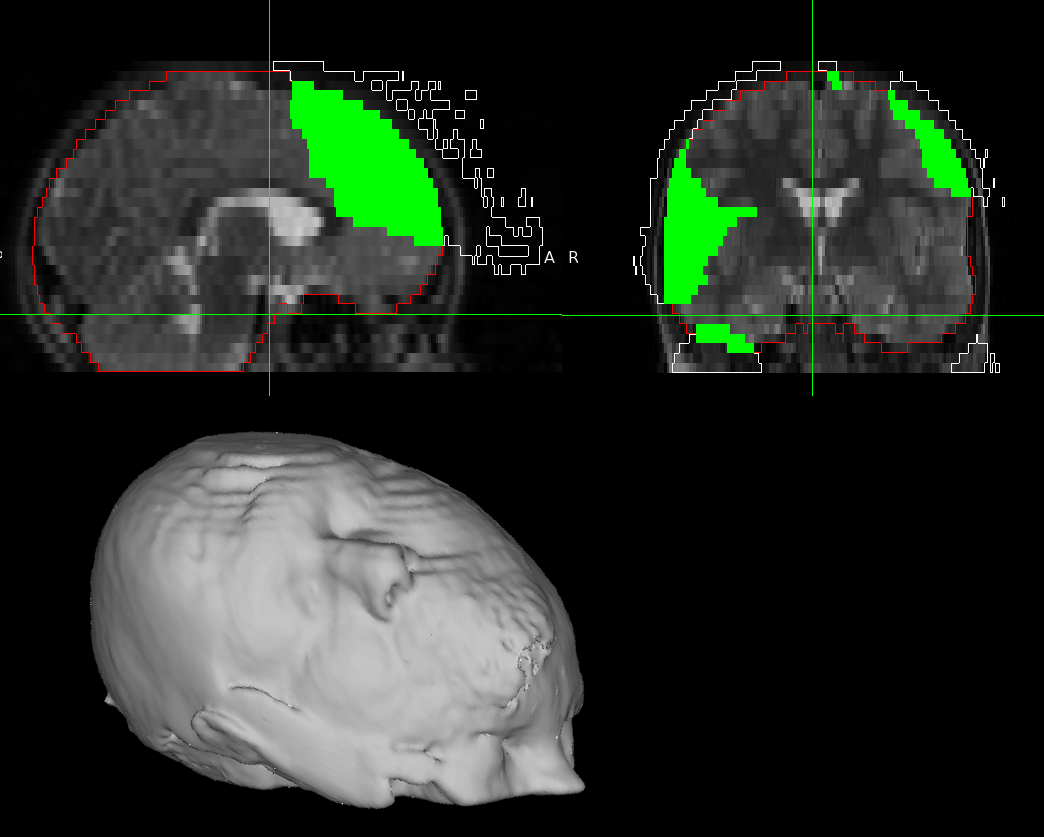

One of the many reasons I love mri_reface is that it can accomodate DICOM in and out! BUT, I think I'm running into an issue with registration failure due to an image origin that is too low. In the attached picture, the underlying image is a TSE T2-weighted image, the image origin is marked with the green crosshair, the white outline is the difference between the original image and the _deFaced.nii (essentially where the refaced mask is), the red outline is a quick brainmask using Freesurfer synthstrip, and the green is where the refacing and brainmask overlap. The picture on bottom shows the refacing on top of the head.